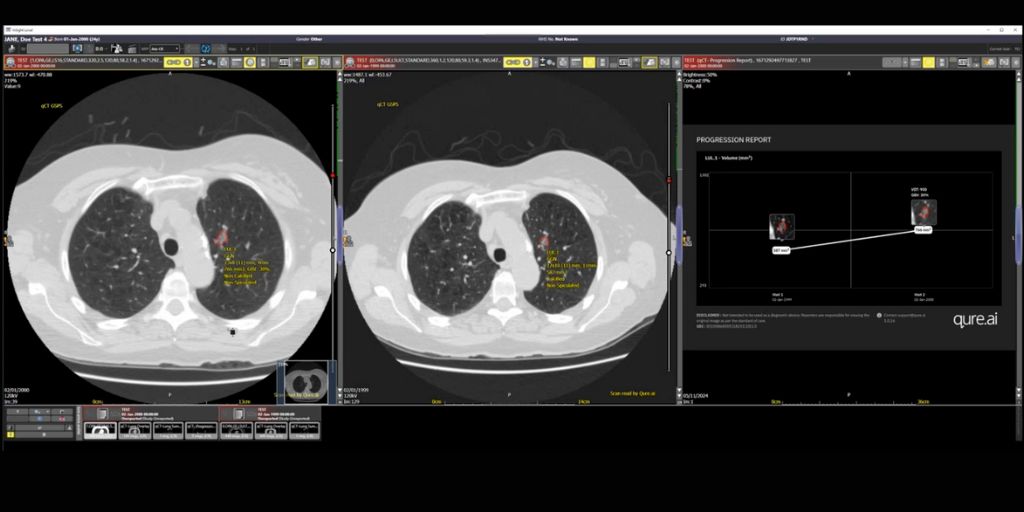

“qCT has been designed to provide clinical decision support in the detection, characterisation, quantification and monitoring of lung nodules. It can also pull patient images from prior examinations to provide comprehensive nodule management and support progression monitoring over time. This makes it easier for the clinician to assess the growth of nodules with standardised data for volumetry assessment and an auto assigned malignancy risk score of pulmonary nodules using the Brock model/ BTS Guidelines,” continues Surabhi Srivastava.

qCT from global healthcare AI innovator Qure.ai, is part of an end-to-end AI-powered lung cancer care continuum suite of solutions for chest X-ray and CT, to detect, measure and track lung nodules.